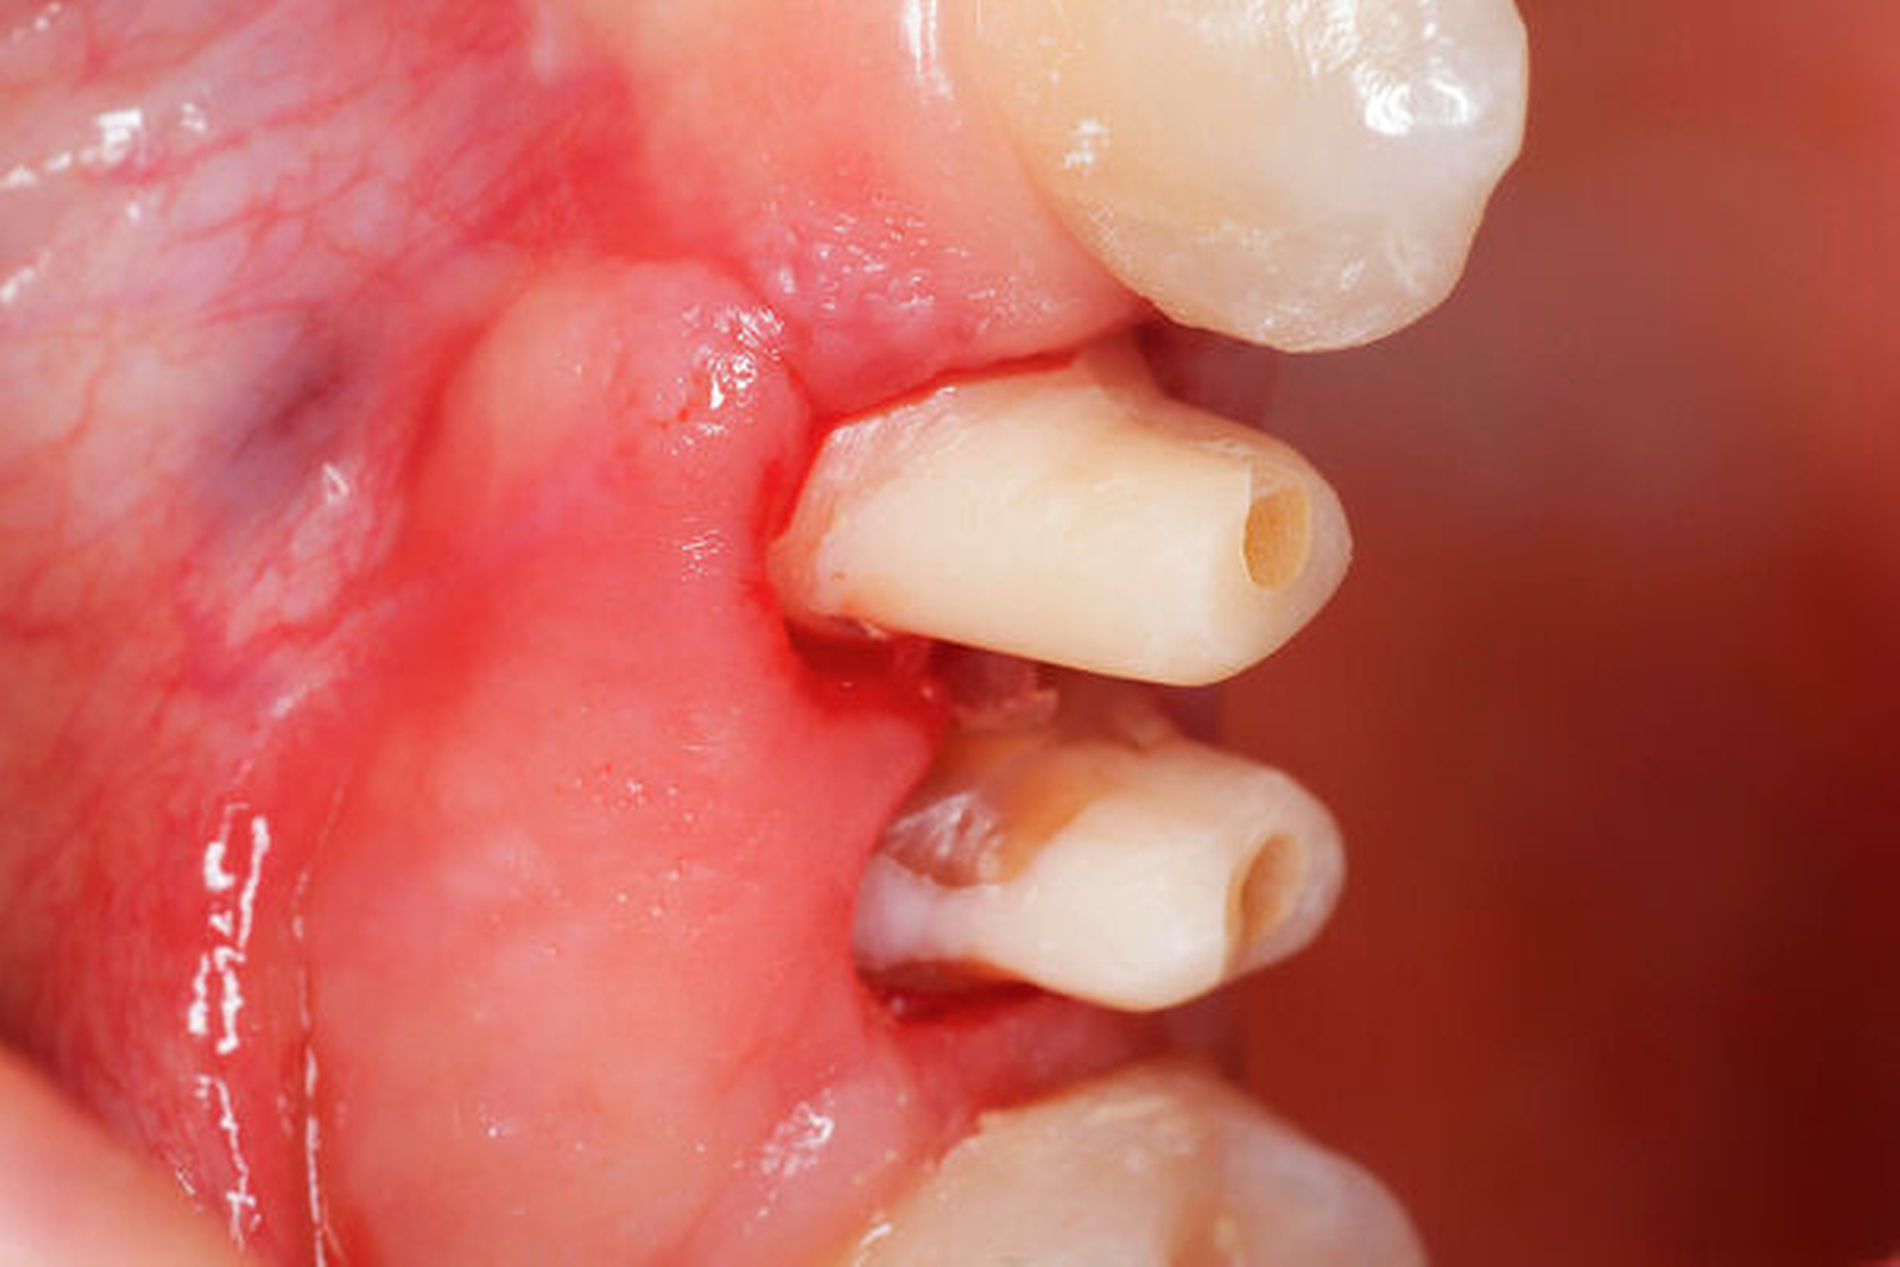

Der extraorale Befund war bis auf ein Hämatom im Kinnbereich unauffällig. Eine Kiefergelenksfraktur wurde bereits am Vortag im unmittelbar nach dem Unfall aufgesuchten Klinikum Ludwigshafen ausgeschlossen. Intraoral zeigte sich ein vollständiges, kariesfreies Gebiss mit Z. n. abgeschlossener kieferorthopädischer Therapie. Die Zähne 14 und 15 hatten einen Lockerungsgrad II sowie eine alio loco angebrachte flexible SÄT-Drahtschienung. An den Zähnen 16, 26, 45 und 46 wies die Patientin z. T. ausgedehnte Schmelz-Dentin-Abscherungen auf. Nach Entfernung der Schienung 14 Tage später zeigten sich die komplizierten Kronen-Wurzel-Frakturen an 14 und 15.

Nach gründlicher Aufklärung und Beratung der Patientin und ihres Vaters wurde zunächst die Füllungstherapie der Zähne mit Schmelz-Dentin-Frakturen sowie die Mikroskop- gestützte endodontische Behandlung der beiden Prämolaren durchgeführt. Hierfür wurden die mobilen vestibulären und oralen – lediglich an der Gingiva gestielten – Zahnfragmente an 14 und 15 zunächst belassen, um eine möglichst gute Trockenlegung zu erreichen, da diese Fragmente sich mithilfe der Kofferdamklammer so gut adaptieren ließen, dass eine ausreichend gute Trockenlegung ermöglicht wurde.

Nach der endodontischen Behandlung der Zähne 14 und 15 erfolgte die chirurgische Entfernung des mobilen vestibulären beziehungsweise oralen Kronenfragments sowie der infragingival frakturierten Wurzelanteile. In der gleichen Sitzung erfolgte die Aufklappung vestibulär und oral, um nach Trocknung der Zahnstümpfe eine adhäsive Befestigung von zuvor auf dem Modell gefertigten Drahtschlaufen (018``Stahl: Dentalline, Deutschland) zu ermöglichen. Diese wurden mittels dual härtendem Composit (Rebilda DC, Voco) intrakanalär verankert. Mithilfe eines weiteren, an den mesialen und distalen Nachbarzähnen adhäsiv angebrachten Drahtes (17x25 TWIST, 3-fach verseilt; Dentalline, Deutschland) und einer elastomeren Kette (Energy Chain, Rocky Mountain Orthodontics, USA) war es nun möglich, die Wurzelreste orthodontisch aus den Alveolen zu extrudieren. Hierzu waren über einen längeren Zeitraum mehrere Behandlungstermine nötig, bei denen die Gummizüge entsprechend des Behandlungsfortschritts gewechselt wurden. Des Weiteren erfolgten in regelmäßigen Abständen Inzisionen im PA-Spalt, um eine Mitwanderung des Knochens zu vermeiden. Anders als bei festsitzenden Multibandapparaturen ist eine definitive Kraftangabe bezüglich der Extrusion nicht möglich, da sich die Kräfte mit fortschreitendem Extrusionsgrad und je nach verwendeter elastomerer Kette ändern.